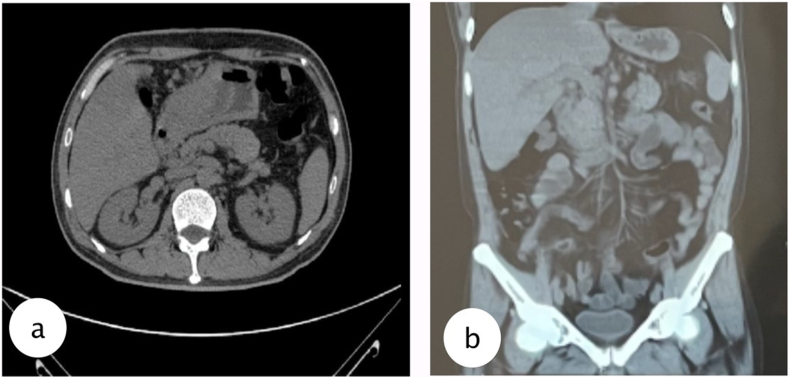

Percutaneous drainage was performed under local anesthesia using 16 FR nasogastric tube (NGT) guided with 5 mm laparoscopic trocar to the most prominent area which could be done in outpatient clinic, and the tube connected to reservoir bag to collect the product. Due to its size we inserted the tube guided from the MSCT results. Evaluation was done every week of the drain product and gradually it reduced after 2 months until the product was negative and the drain could be removed. Results from MSCT evaluation were favorable.

Our patient after 2 months follow-up has no complaints, and when the abdominal lump was gone, then tube could be removed. The patient was evaluated with MSCT showing the biloma was diminished with favorable outcome from the percutaneous drainage. The solution to resolving this complication is early diagnosis and percutaneous drainage under CT guidance. The current body of knowledge is still small, and further research is required to recognize risk factors and prevent future biloma occurrence, reducing morbidity and mortality of the patients.